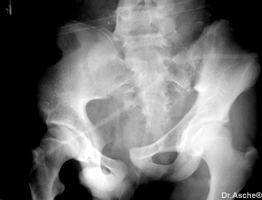

Vordere Beckenringfraktur. Durch Computertomografie und Kernspintomografie wurde eine complette hintere Beckenverletzung ausgeschlossen. Diese Symphysensprengung läßt sich leicht mit Beckenfixateur stabilisieren. Hier ist die Belastung meist schon nach 2 Wochen möglich. Liegedauer des Fixateur 6-8 Wochen.